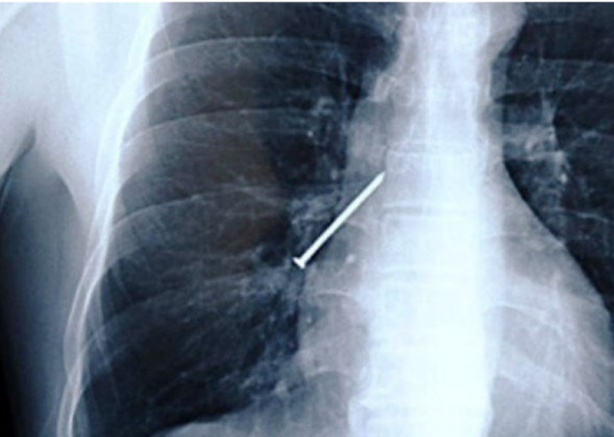

Ağzına çivi saplanan hastanın ameliyata alınmadan önce çekilen röntgen filmi...